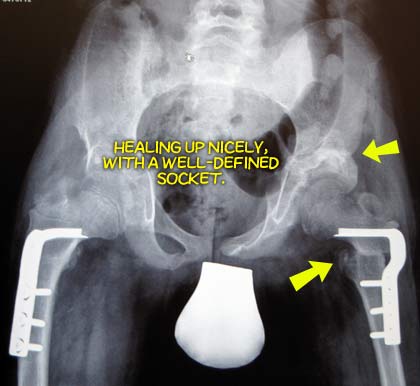

Well, today was the long, long awaited check-up day for Jon. Not unexpectedly, the x-rays look good, and Dr. Narayanan is very happy with how everything looks.

TODAY

Our bionic boy.